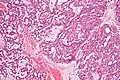

Polymorphous low-grade adenocarcinoma. H&E stain.

Polymorphous low-grade adenocarcinoma. H&E stain. Micrograph of a polymorphous low-grade adenocarcinoma. H&E stain.

Micrograph of a polymorphous low-grade adenocarcinoma. H&E stain.